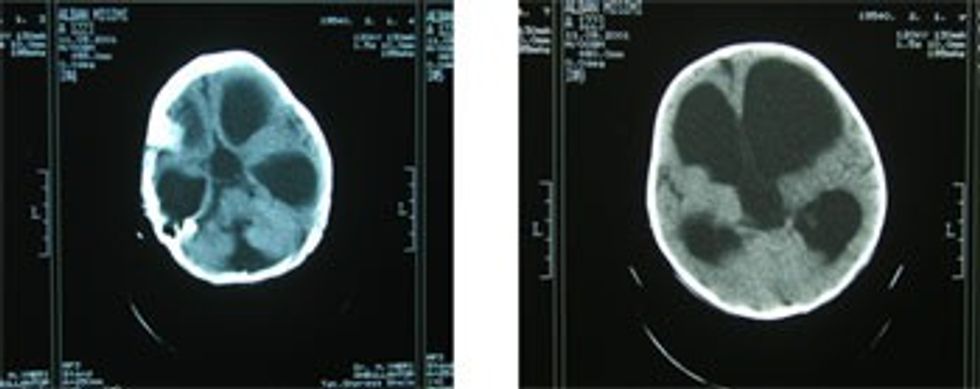

(majtas) Dandy Walker. Hidrocefalus treventrikular

(djathtas) Hidrocefalus tipi obstruktiv

(majtas) Hidrocefallus obstruktiv, tipi hipertensiv. Proces expansiv infratentorial me mbyllje gati komplete të ventrikulit të katërt

(djathtas) Hidrocefallus obstruktiv